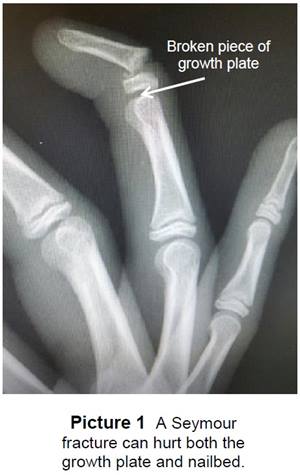

A Seymour (see-more) fracture is a break in the bone at the end of the finger or toe at the first

joint (Picture 1). It often happens when a finger

or toe is crushed or bent back too far.

In children, there is a growth plate at the end of

their bones. It is the weakest part of the bone

until the bone stops growing. Where a nail starts

to grow (nailbed) is located near the growth plate.

With a Seymour fracture, when a nailbed gets crushed, it can push and trap skin (tissue) in between the broken growth plate and the bone.

This may affect healing and cause problems

with how the bone and nail grow.